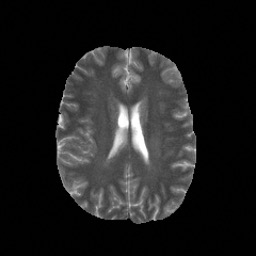

Denoising diffusion probabilistic models (DDPMs) have achieved unprecedented success in computer vision. However, they remain underutilized in medical imaging, a field crucial for disease diagnosis and treatment planning. This is primarily due to the high computational cost associated with (1) the use of large number of time steps (e.g., 1,000) in diffusion processes and (2) the increased dimensionality of medical images, which are often 3D or 4D. Training a diffusion model on medical images typically takes days to weeks, while sampling each image volume takes minutes to hours. To address this challenge, we introduce Fast-DDPM, a simple yet effective approach capable of improving training speed, sampling speed, and generation quality simultaneously. Unlike DDPM, which trains the image denoiser across 1,000 time steps, Fast-DDPM trains and samples using only 10 time steps. The key to our method lies in aligning the training and sampling procedures. We introduced two efficient noise schedulers with 10 time steps: one with uniform time step sampling and another with non-uniform sampling. We evaluated Fast-DDPM across three medical image-to-image generation tasks: multi-image super-resolution, image denoising, and image-to-image translation. Fast-DDPM outperformed DDPM and current state-of-the-art methods based on convolutional networks and generative adversarial networks in all tasks. Additionally, Fast-DDPM reduced training time by a factor of 5 and sampling time by a factor of 100 compared to DDPM. Our code is publicly available at: https://github.com/mirthAI/Fast-DDPM.